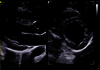

Visualisez clairement la délimitation de la paroi myocardique sans réglages complexes, dès le premier scan.

Vous recherchez une solution d’imagerie cardiaque qui allie fiabilité et simplicité d’utilisation. Le système d'échographie ultra-premium Vivid Pioneer se distingue par ses capacités avancées. Il est désormais doté de cSound™ Pioneer, une plateforme de nouvelle génération conçue pour améliorer la clarté et la définition pour tous les type de patients. Avec un traitement d'image amélioré et une formation de faisceau adaptative, elle vous accompagne dans vos diagnostics qu'ils soient standards ou complexes.

Avec une qualité d'image exceptionnelle qui accentue les contours, augmente la clarté et améliore la définition entre les structures, Vivid Pioneer offre une base optimale pour que l'IA délivre tout son potentiel. Simplifiez et rationalisez les mesures et la quantification en toute confiance. Obtenez des résultats cohérents et fiables pour tous les utilisateurs.